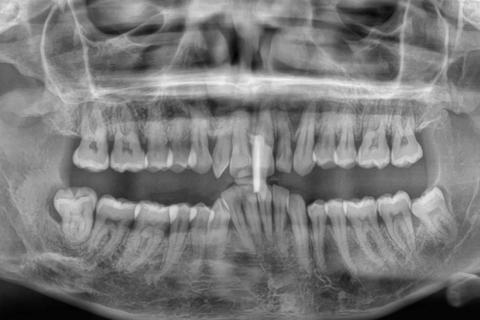

Panoramic X-Ray Showing Generalized Bone Loss and Infection Risk Case Analysis

What Is Seen in This Case

The panoramic X-ray shows both upper and lower jaws with multiple teeth present, but the bone levels around many tooth roots appear reduced. In several areas, the bone looks uneven and lower than normal, especially around the front teeth and molar regions. There is also evidence of previous dental treatment on at least one tooth.